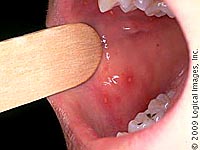

|

Bóng nước của bệnh tay chân miệng và các vị trí bóng nước thường xuất hiện. |

Phụ nữ mang thai cũng có thể bị nhiễm bệnh. Tuy không ảnh hưởng đến thai nhi, song nếu bà bầu bị nhiễm virus gây bệnh trước khi sinh, mẹ có thể truyền virus cho con. Thời gian ủ bệnh thường từ 3 đến 7 ngày. Biểu hiện thường thấy là sốt, đau họng, biếng ăn, mệt mỏi, nổi bóng nước. Bóng nước ban đầu chỉ là những chấm đỏ nhỏ sau đó biến thành bọng nước và vỡ ra. Bóng nước thường xuất hiện ở lưỡi, nướu (lợi) và bên trong má. Ngoài ra còn thấy ở lòng bàn tay hoặc lòng bàn chân, một số trường hợp nổi ở mông. Cũng có một số trường hợp bóng nước chỉ xuất hiện ở miệng. Nếu bệnh do coxsackievirus A16 gây nên thường tự lành sau một tuần. Nhưng nếu nhiễm enterovirrus 71, trẻ có thể bị biến chứng viêm màng não, viêm cơ tim cấp, viêm phổi.